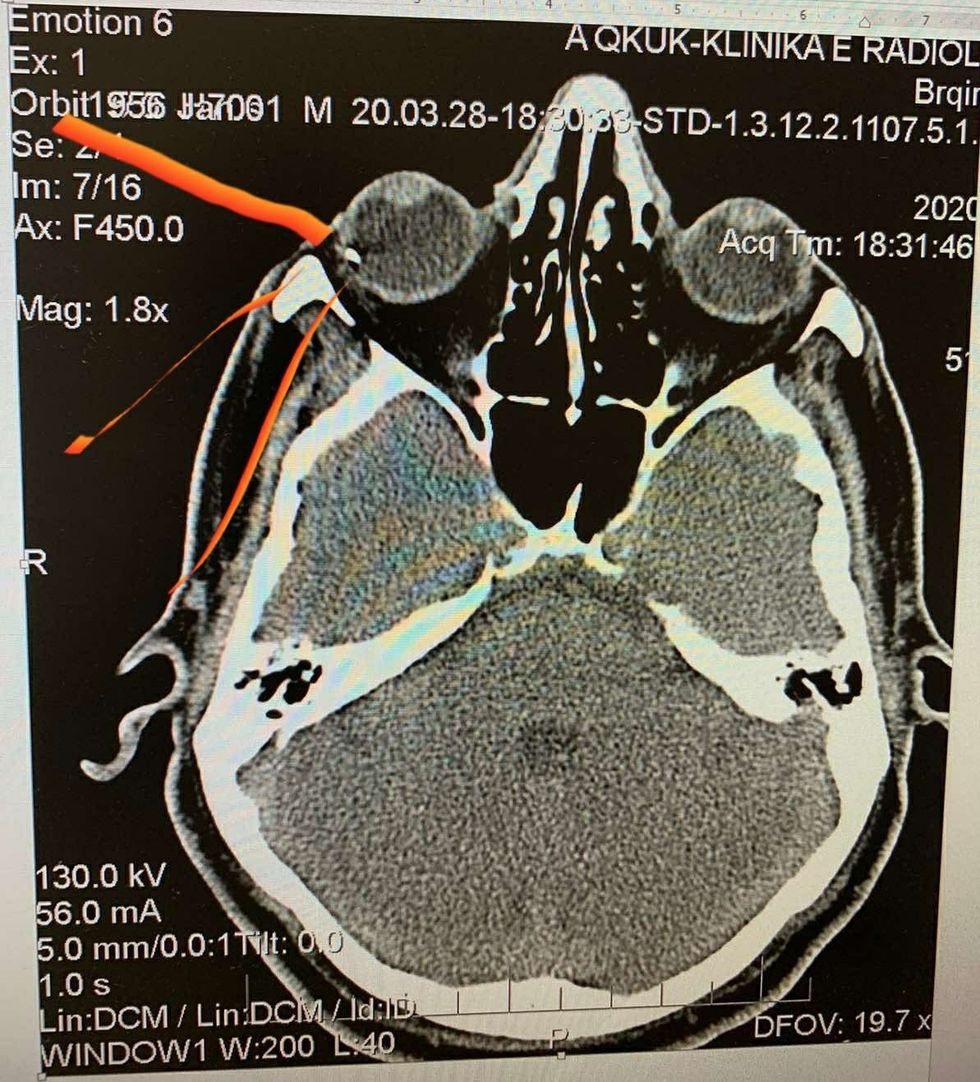

Në njoftim thuhet se kjo ndërhyrje është kryer tek pacienti B.A (1956), syri i të cilit pas CT-së kontrolluese është në gjendje të mirë, transmeton Telegrafi.